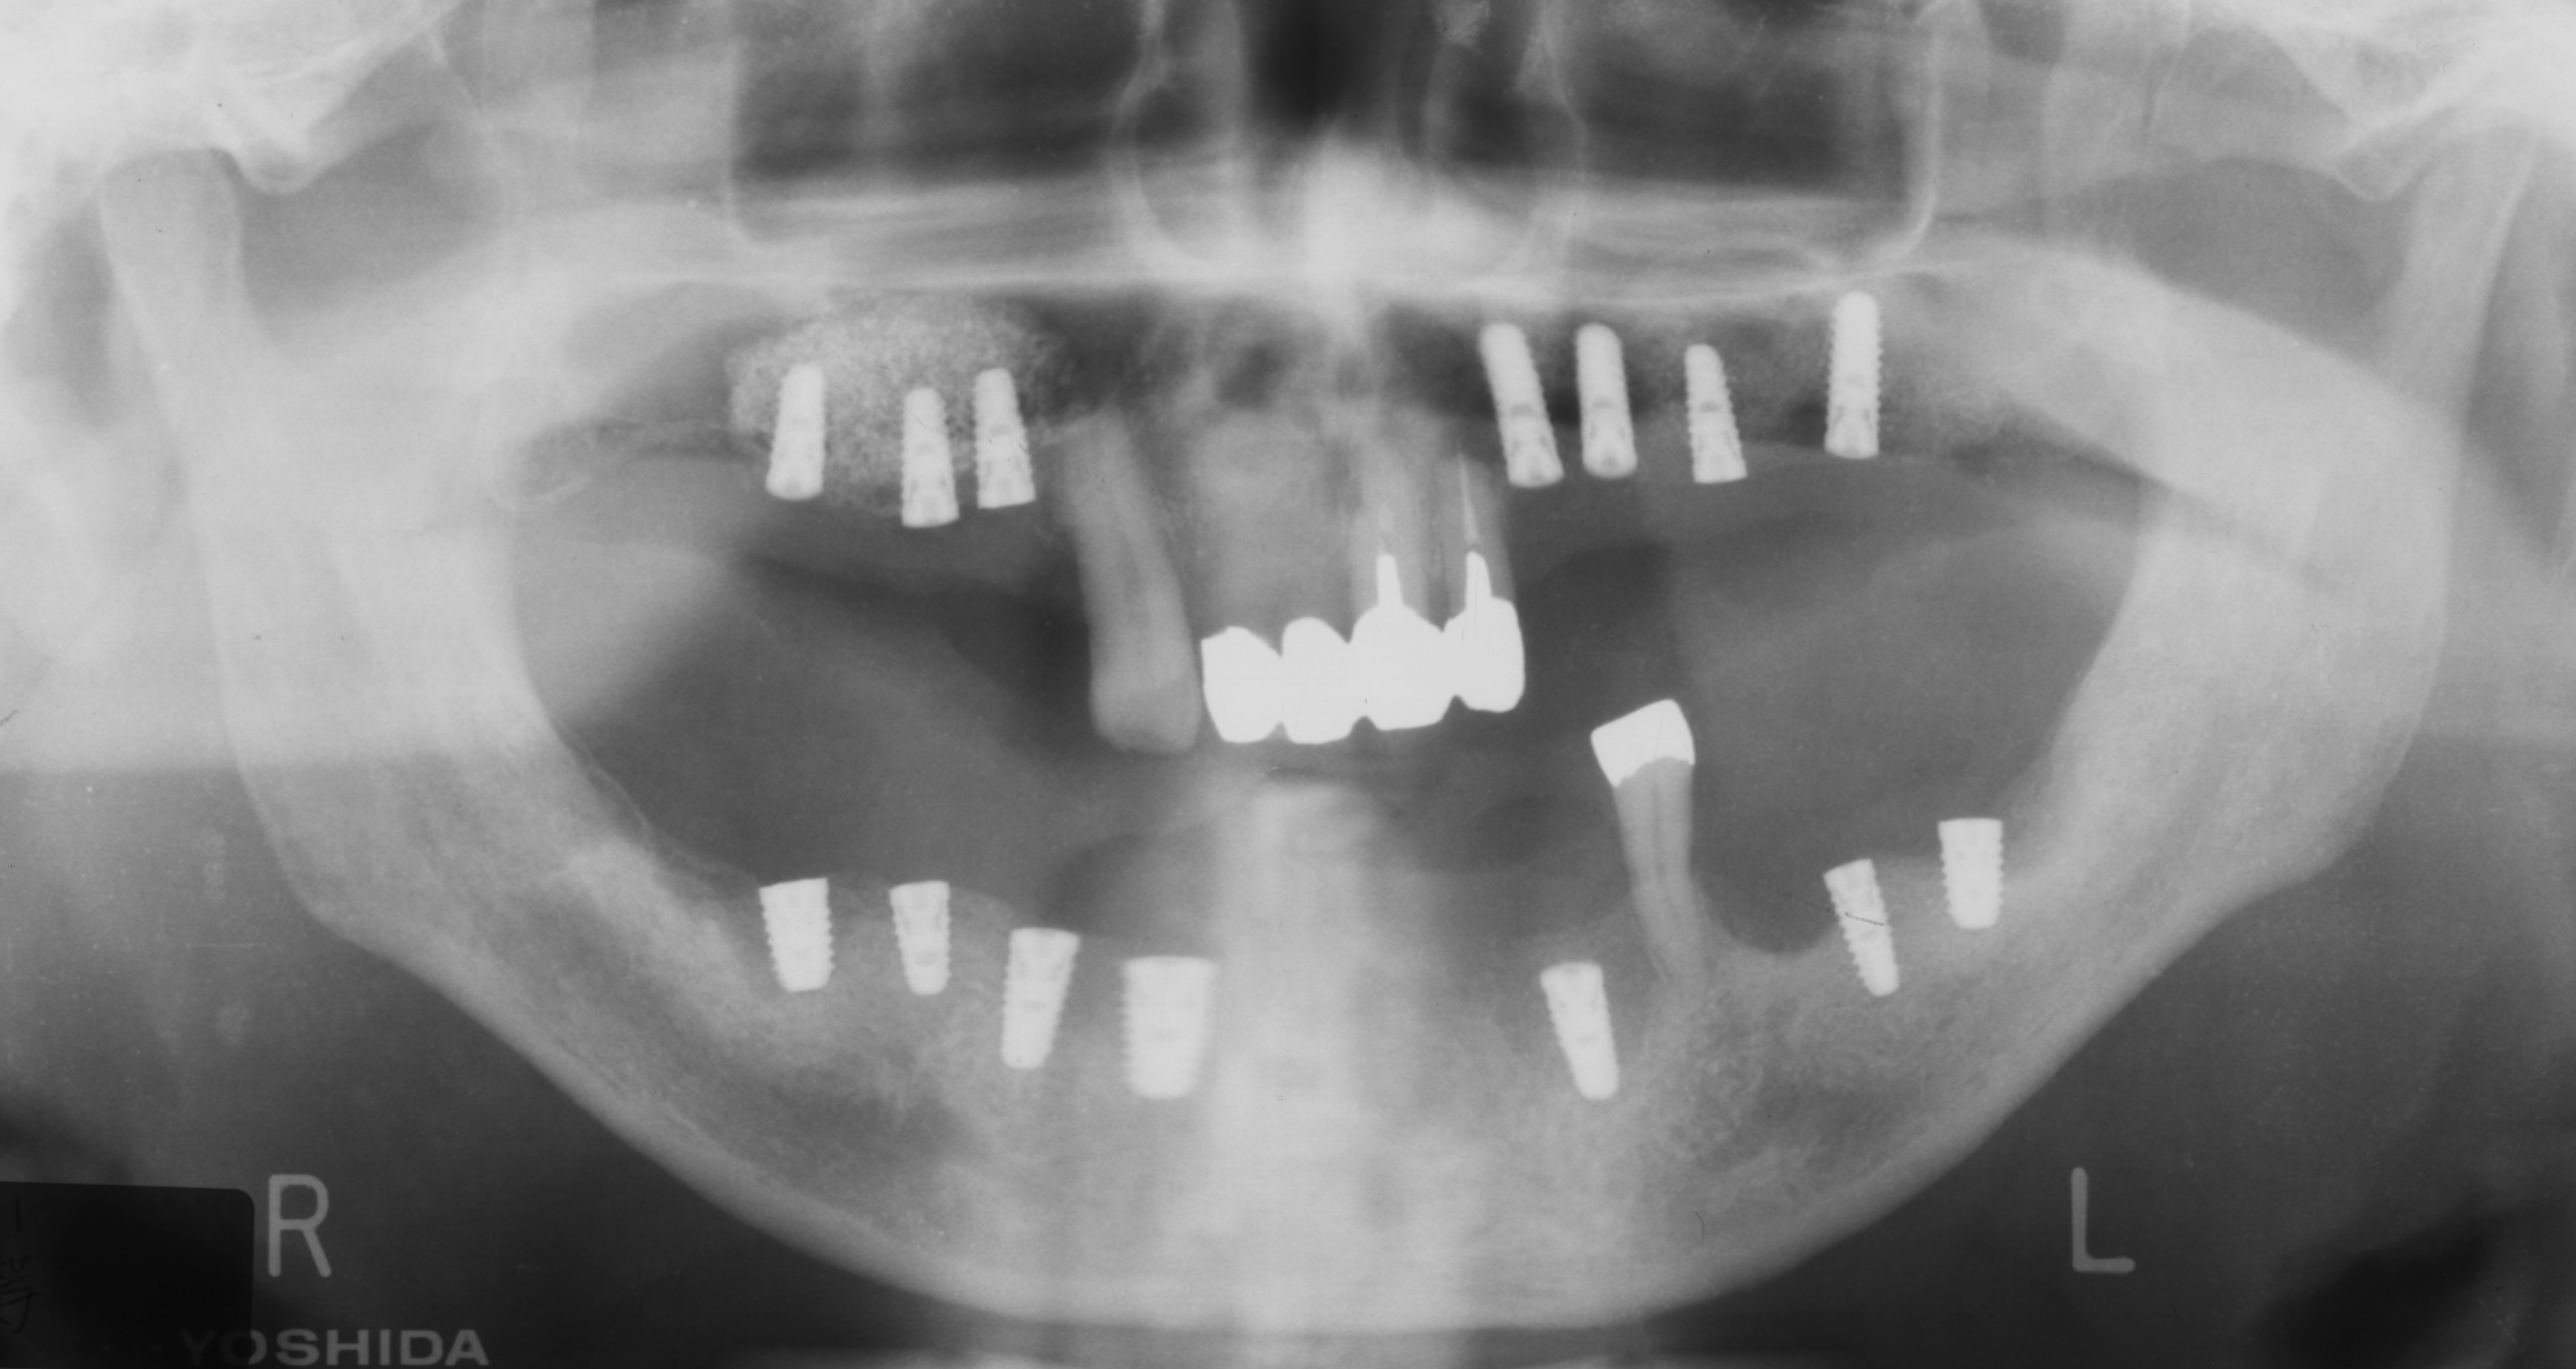

重度歯周病患者にインプラント治療(続き)

インプラント、重度歯周、サイナスリフト、ネジ山

重度歯周病患者にインプラント治療

重度歯周病

骨が足りない

インプラントが動く